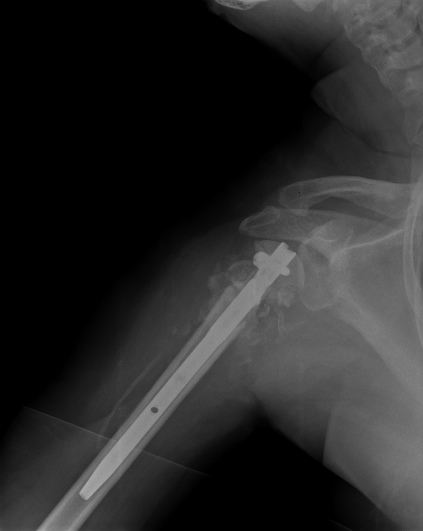

Пошли на операцию, будучи готовыми как к фиксации, так и к протезированию. Головка с краев была неполная, но для двух винтов места хватило. Сделали что-то вроде гемиартропластики собственной головкой. Бугорки фиксировали, как при эндопротезировании.

Снимки вот.

The nail looks a little proud. Will it not come in the way of mobilisation of the shoulder? What is your postop protocol in this case?

Dear Alex,

But if I should act as the devil’s advocate, I suppose, actually hope, the head was not totally avascular, there is some graft added, there might be either some faint impingement of the most proximal screw against the acromion or even the nail is a little proud cranial the bone ( or even the cartilage ? ). Maybe the end could be an avascular necrosis and it might be well tolerated ! Lots of bad possible outcomes and some possitive one.

In any case, you have procured yourself with the best of all possible morphologies should revision to a hemiarthroplasry is ever deemed to be done.

действительно интересен протокол послеоперационного ведения и почему выбран несколько нетрадиционный способ фиксации? В случае закрытой операции преимущества есть, а здесь? Пластина более адекватна, как кажется, как минимум из-за количества винтов? Согласен с мнением коллеги по поводу костной пластики: bone stock и ! офсет, что может быть неплохо при непонятной неврологии.

Ты нашу тактику знаешь, мы бы поставили пластину. Хотя без пластины, но получилось здорово!

Там видно ты применил Синтезовский MultiLoc гвоздь с screw in screw технику. Главное, ты собрал фрагменты и если понадобится следующие операции, тогда будет легче...